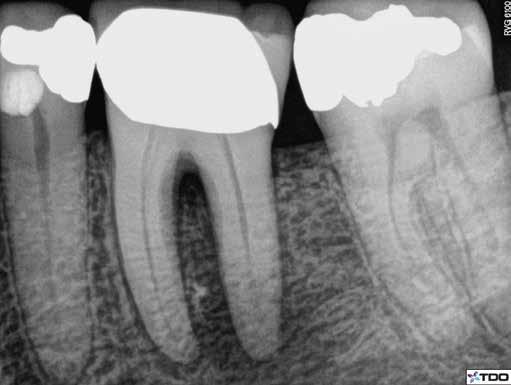

Egy 38 éves nőbeteg a korábban kezelt jobb felső második kisőrlőfogából (1.5) kiinduló mérsékelt fájdalom miatt jelentkezett rendelésünkön. A kórtörténetében jelen panasza szempontjából releváns információ nem szerepelt. A beteg a klinikai vizsgálat során vertikális kopogtatásra enyhe érzékenységet jelzett. A kérdéses fog körül mérhető szondázási mélység és a fogmobilitás fiziológiás volt. Periapicalis röntgenfelvételen egy, a fog gyökércsúcsán túl presszálódott betört gyökérkezelő műszerből származó eszközfragmentumot láttunk (2. a. ábra). A preoperatív CBCT-felvétel a buccalis csontlemez épségét igazolta (2. b-c. ábra). A fog revíziója öt hónappal korábban történt. A már előzőleg gyökérkezelt, gyökértömött, majd revideált 1.5-ös fog esetében a diagnózisunk periodontitis periapicalis symptomatica volt. A periapikális elváltozás kezelése érdekében navigált endodonciai mikrosebészeti beavatkozást végeztünk.

a-m. ábrák: Preoperatív röntgenfelvétel (a) és preoperatív CBCT-felvétel a jobb felső 5-ös (1.5) fogról, sagittalis (b) és axialis (c) nézetek. Az intraorális szkennelés során kapott STL-fájl (d). A 1.5-ös fog navigált endodonciai mikrosebészeti beavatkozásához tervezett sablon (e). A 1.5-ös fog navigált endodonciai mikrosebészeti beavatkozásához nyomtatott sablon (f). Teljes vastagságú mucoperiostealis lebenyt emeltünk (g). A sablont a helyére illesztettük, és a csontablak határait jelöltük (h). A fog gyökerén kívül eső, betört eszköz a 1.5-ös fog periapicalis régiójában (i). Az eltávolított betört eszköz (j). A rezekció, retrográd preparáció és a TotalFill BC RRM Fast Set Putty anyaggal elkészített retrográd gyökértömés utáni röntgenfelvétel (k). A lebenyt varratokkal rögzítettük (l). A kétéves kontroll során készített röntgenfelvétel (m).

gítségével tovább módosítottuk. Az így kapott sebészi sablon egyértelműen meghatározta a periapikális terület eléréséhez szükséges csontablak határait (2. e-f. ábra) Helyi érzéstelenítést követően teljes vastagságú mucoperiostealis lebenyt képeztünk, majd a buccalis csont feltárását követően (2. g. ábra) a sablon segítségével bejelöltük a preparálandó csontablak határait (2. h. ábra). A csontablak kialakítása során Piezotome CUBE LED kézi-darabot alkalmaztunk, majd a leemelését követően a betört eszközt megkerestük (2. i. ábra) és eltávolítottuk (2. j. ábra). A rezekciót ultrahangos megmunkáló fejekkel (ACTEON) végeztük, majd retrográd preparáció következett.

A retrográd gyökértömés elkészítése során TotalFill BC RRM Fast Set Putty-t (FKG) használtunk (2. k. ábra). A lebeny széleit 5/0-s Prolene varratokkal egyesítettük (2. l. ábra). A varratok a műtétet követően 72 órával kerültek eltávolításra. A beteg két évvel később kontrollröntgen készítése céljából érkezett rendelőnkbe. A vizsgálat során a fog tünetmentesnek és funkcióképesnek bizonyult (2. m. ábra).